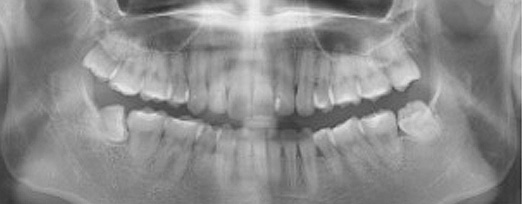

치주치료 전후사진

B

A

치주염 단계별 증상

건강한 상태

치아 주위의 잇몸이 핑크색을 띄며, 잇몸에서 피가 나지 않음.

스케일링을 6개월 ~ 1년 주기로 받고 올바른 칫솔질로 건강한 치주 조직을 유지

치은염 (초기~중기)

치아 주위의 잇몸이 붉게 부어 있으며, 칫솔질 등을 할 때 피가 남.

스케일링 주기의 조절이 필요할 수 있으며, 올바른 칫솔질을 시행하여야 함.

치주염 (중기~말기)

주기적으로 잇몸이 붓고 피가 나며, 욱씬하거나 우리한 통증이 나타남.

치주치료 및 정도에 따라 치주수술(잇몸수술)이 필요함. 향후 관리 정도에 따라 3~6개월 간격으로 내원하여 유지치료를 시행하여야 함.

치주염 (말기)

잇몸이 항상 부어 있으며, 이가

흔들리는 정도가 점점 심해짐.

치주치료가 필요하며, 정도에 따라 치아를 발치하여야 할 수 있음.